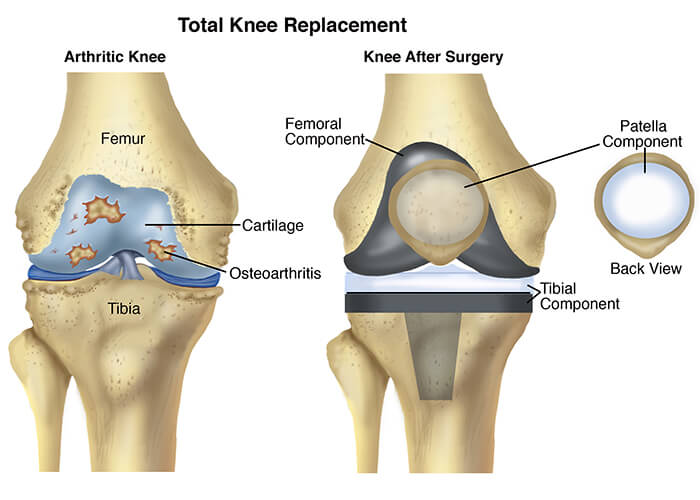

Проблемы с коленным суставом: флоттация и лечение